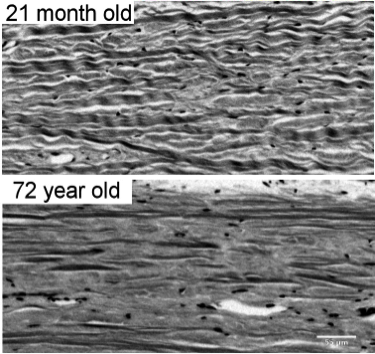

Age is one of the main risk factors for many diseases. We work to understand how aging affects the eye at the microstructural level.

We have developed techniques to visualize the density and orientation of collagen fibers of soft tissues in high resolution (~um). Using these techniques we have measured microstructural properties of the tissues, such as the patterns of collagen crimp, that underlie the complex nonlinear properties of the eye.